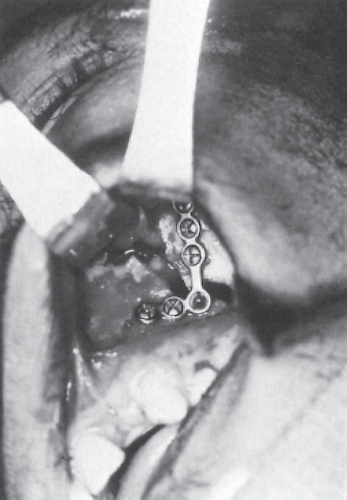

Frequently, the lateral wall of the maxillary antrum is comminuted even when the other projections of the arcs of contour suffer simple fractures or separation of a suture line. In such cases, a single craniofacial miniadaptation plate attached across the comminuted area is sufficient for lateral wall reconstruction ( Fig. 62.4 ). Because the fixation device is not resisting heavy occlusal forces, as would be the case with a Le Fort fracture, insertion of only two screws into the body of the zygoma above and at the maxilla below is required for stability. In addition, a prebent L-shaped plate may be used to facilitate placement of screws below the fracture lines if there is concern for the root tips of the maxillary teeth.